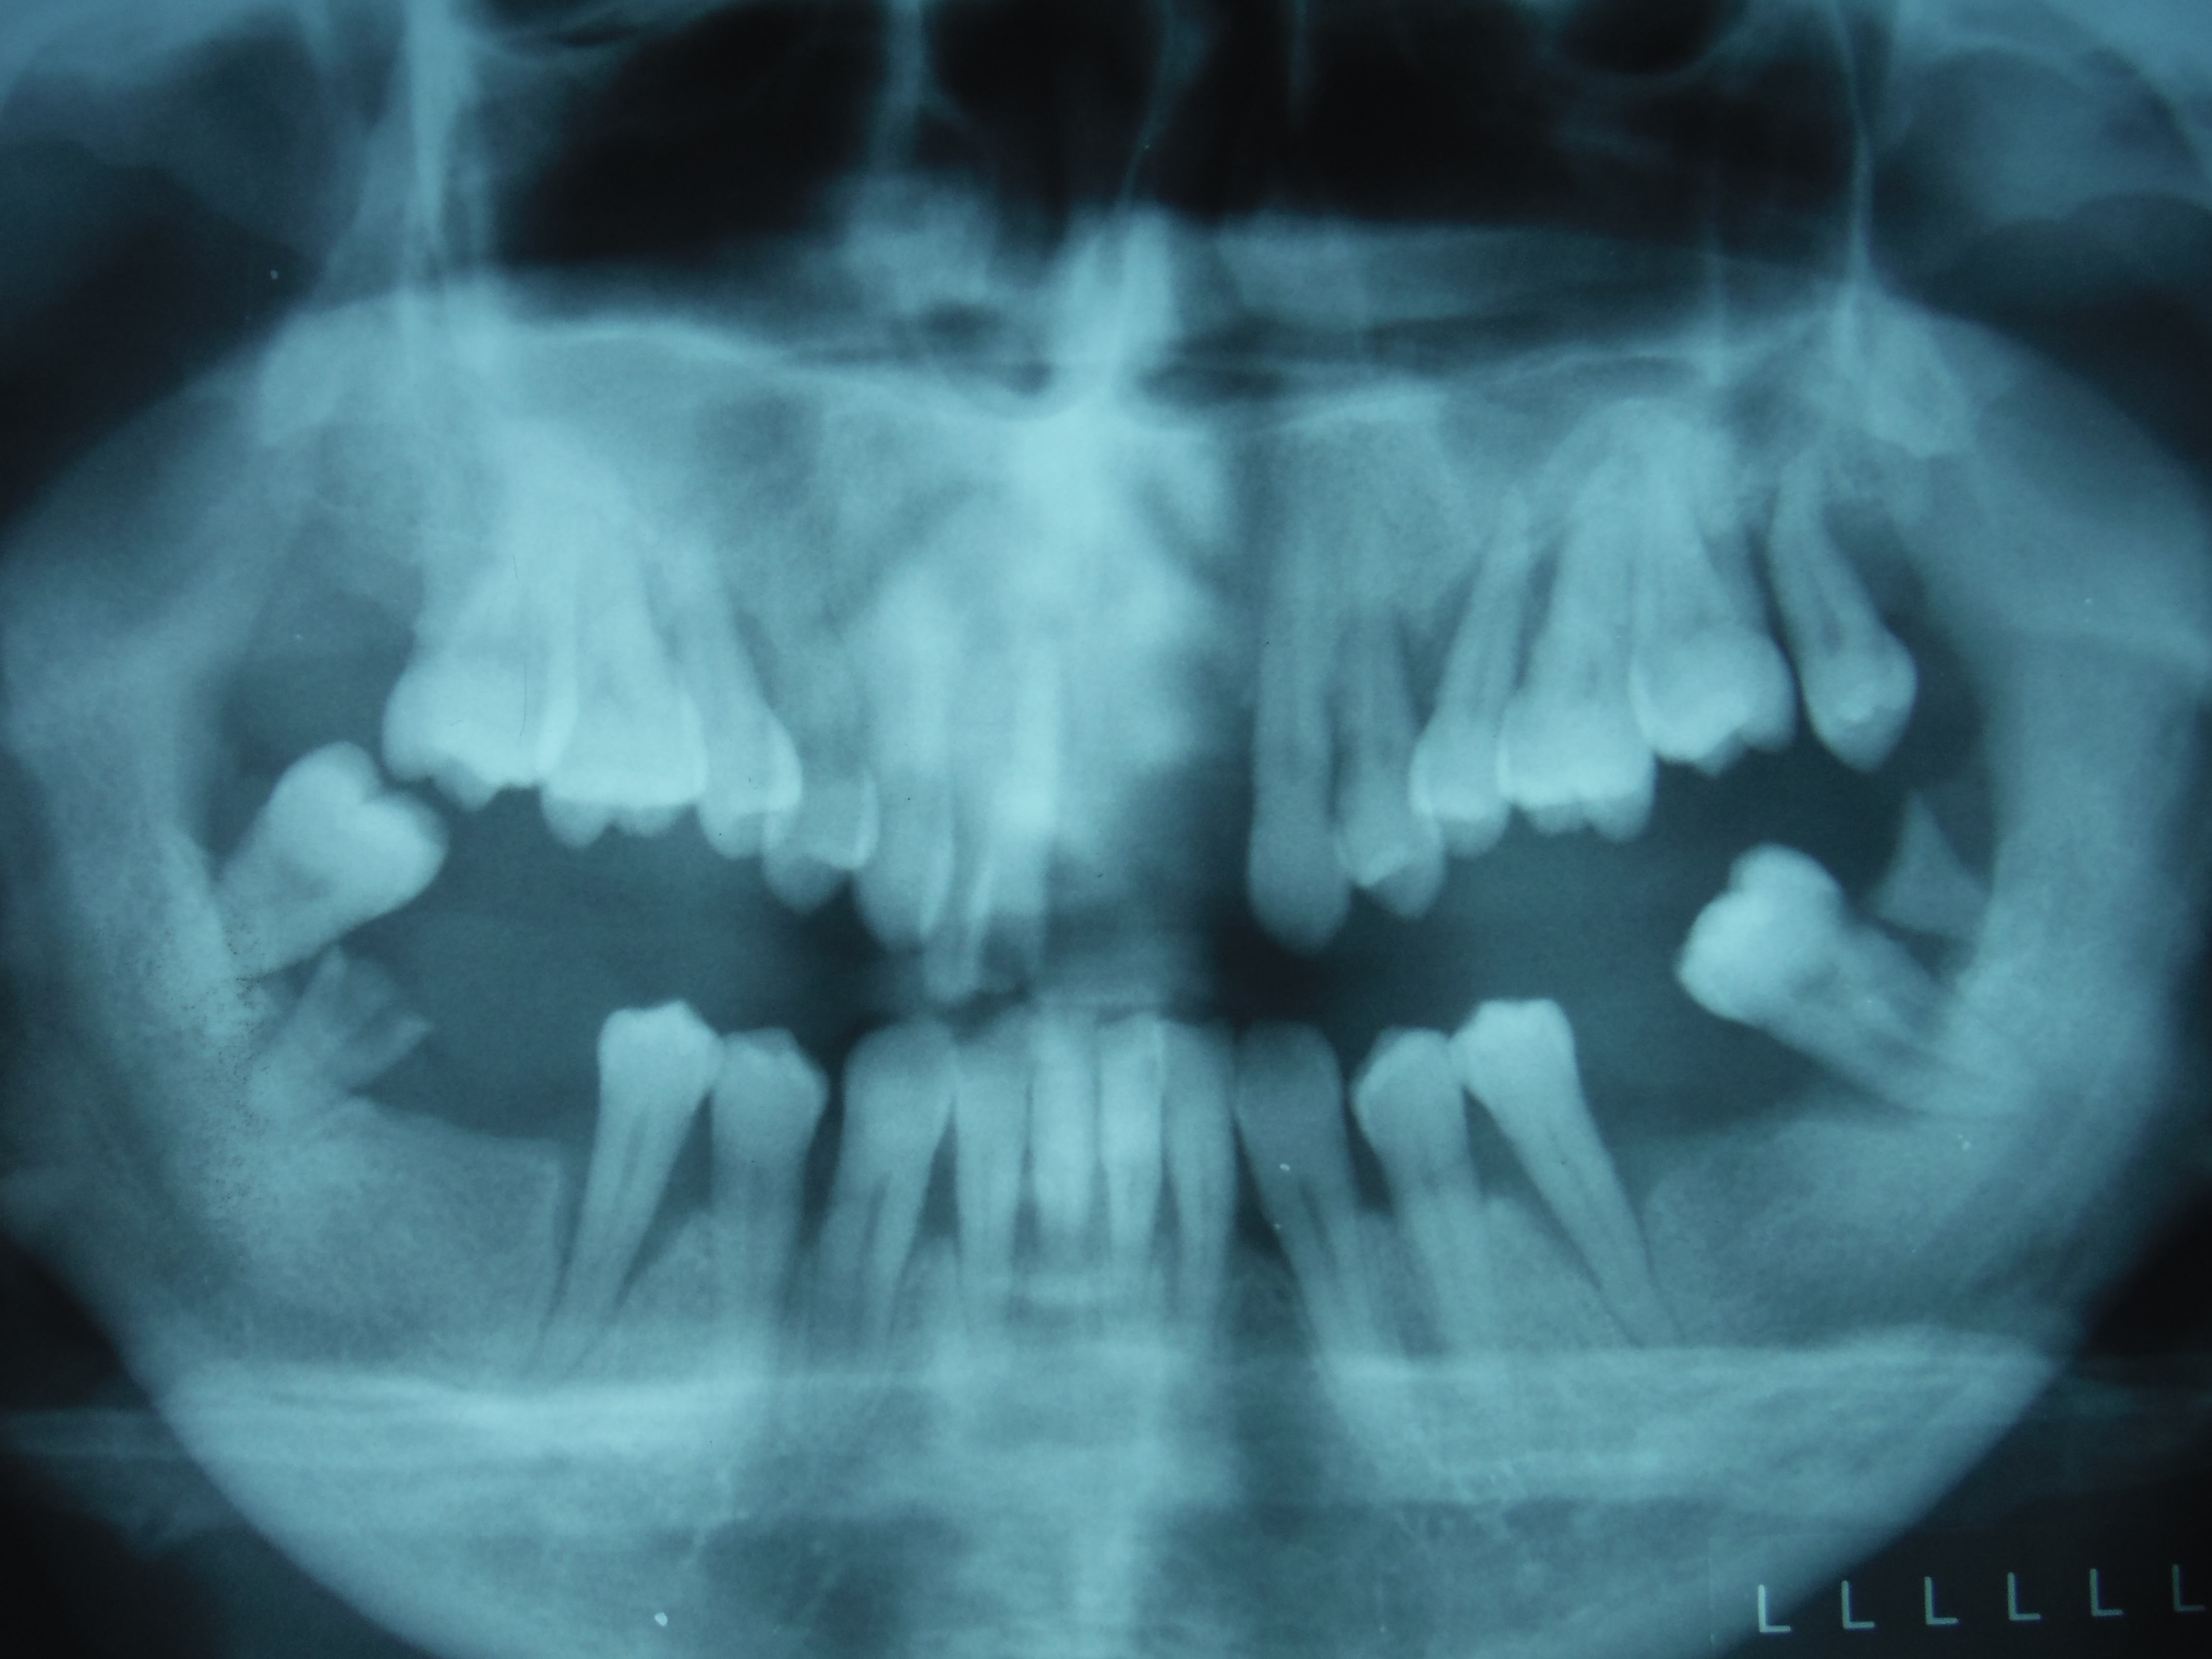

Vulpi si tu en as l'occasion, est ce que tu pourrais mettre la pano de ton cas ? Pour voir le niveau osseux

On voit pas trop sur la pano mais y a plusieurs dents qui ne sont tenues que par quelques mm d'os.

1) surfaçage , les dents mandibulaires sont conservables

2) la réalisation d'une PPA provisoire maxillaire va solliciter encore plus des dents qui ne tiennent pas des masses. Ça ne sera que du bricolage. Et en plus le patient aura eu l'impression d'avoir payé une PPA pour rien puisque toutes ses dents vont bouger et dégager une par une

3) dans ce cas ça me choquerait pas qu'un praticien dise pour le maxillaire

- extraction , complet immédiat

-OU BIEN extraction, implantation immediate et mise en charge immédiate ou précoce SI c'est possible , après annalyse du scanner et l'analyse pré-implantaire

Les 7, PM et C sont exploitables, il n'a jamais été appareillé (et c'est important!), une partielle est préférable, quitte à ce qu'elle soit évolutive.

La pano est moche, très vieux cas, qu'aurais tu fait?

On vire tout le maxillaire, et tout ce qui est postérieur aux 4 à la mandibule. Des crochets sur des 5 mandibulaires qui ont subi un traumatisme occlusal, ça me plaît pas trop. Donc je vire les 5 également.

Complet immédiat, PPA provisoire mandibulaire

Ou encore une solution implantaire au maxillaire , voir même à la mandibule. Après assainissement paro réévaluation et Rdv de maintenance

Au maxillaire j'ai fait un bridge complet, exo de la 8, des inc, endo du reste, SC33... 16 ans après il est toujours là, la patiente a déménagé mais sur la Côte alors tous les étés je prends des nouvelles.

Pour le bas Pap châssis métal évolutif, aujourd'hui elle a un complet.

Il est évident que le maxillaire aussi finira en pac, mais on a gagné des années...